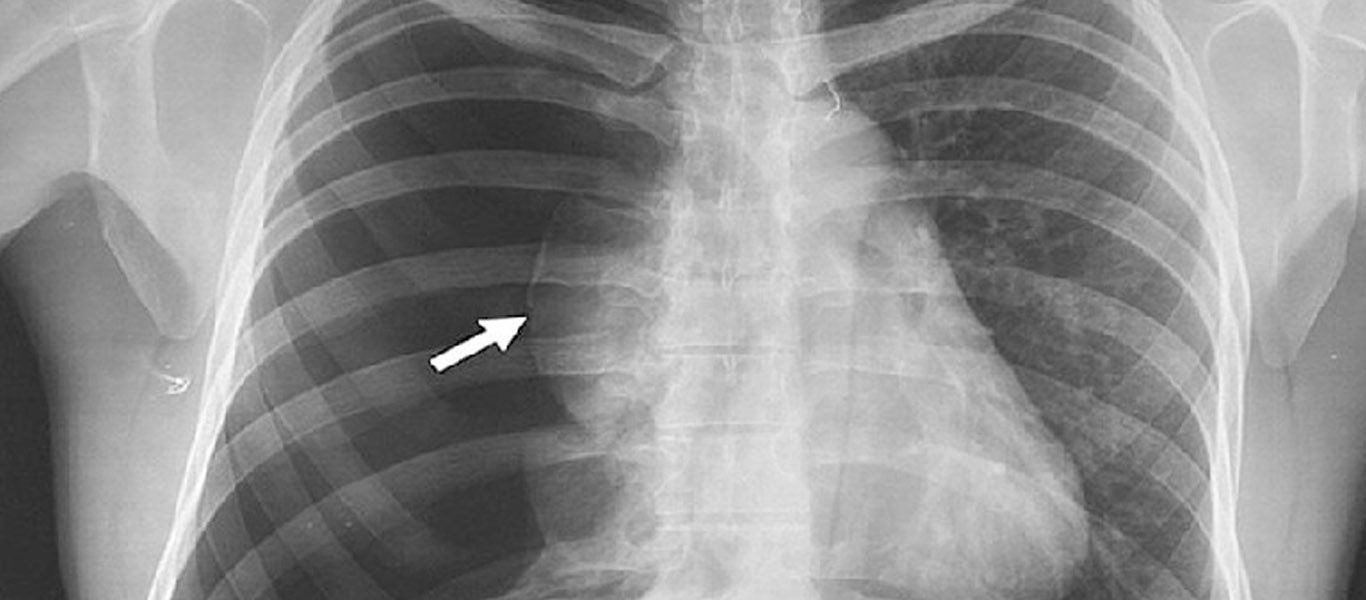

El neumotórax es un colapso pulmonar que se produce cuando se filtra aire dentro del espacio que se encuentra entre la pared torácica y los pulmones (cavidad pleural). El aire presiona sobre los pulmones colapsándolos.

Produce dolor torácico repentino, falta de aire; pudiendo llegar a producir un gran deterioro de la función pulmonar de forma súbita hasta incluso ser un evento que ponga en riesgo la vida del paciente. Este puede ser causado por traumatismos, enfermedades pulmonares ocultas, estar asociado a procedimientos médicos o incluso producirse de forma espontánea sin causa aparente. El mismo se diagnóstica mediante una simple radiografía de tórax.